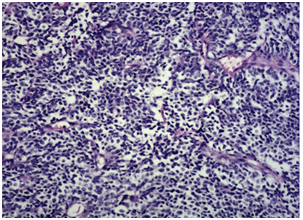

The incidence of prostate cancer (PC) has increased worldwide, allegedly since the accepted use of PSA as a screening tool. Even though most PC are adenocarcinomas, other subtypes have been defined, namely squamous cell, sarcomatoid, urothelial, basal cell, adenoid cystic and small cell carcinoma. Each one of them has specific clinic-pathologic features, distinct clinical relevance and different prognosis.1 The diagnosis of small cell prostate cancer (SCPC) is reached based on the presence of morphological features similar to those found in SCLC, as defined in the 1999 WHO classification criteria of pulmonary neoplasms (Figure 1): proliferation of small cells with unique morphological features, little cytoplasm, poorly-defined borders, finely granular ‘salt and pepper’ chromatin, absent or inconspicuous nucleoli, frequent nuclear molding and a high mitotic rate.2

Figure 1 Histological findings of the prostatic tumor. H&E (x20).2